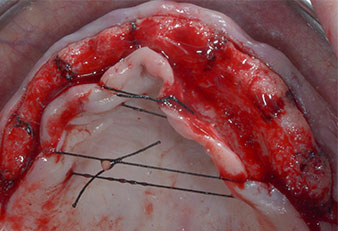

Wegen des relativ harten Knochens (D2) an den Positionen 11 und 21 wurden die 10 mm langen Implantatlager in diesem Bereich abschließend mit einem 4-mm-Spiralbohrer, dem chirurgischen Winkelstück WS-75 L von W&H und dem W&H Implantmed Implantologiemotor in Verbindung mit dem optionalen W&H Osstell ISQ module präpariert. Im Gegensatz dazu wurde der weiche Knochen der Implantatlager im Seitenzahnbereich mit dem Piezomed I3P auf den abschließenden Durchmesser von 3 mm erweitert. Die Implantate wurden dann transgingival eingesetzt, die Einheildauer betrug drei Monate (Abb. 6-10). Die vorhandene Prothese wurde auf vier provisorischen Implantaten abgestützt (Abb. 8).

Abb. 6: Ein 10-mm-Tissue-Level-Implantat wird an Position 21 platziert. Das Implantat an Position 11 und die drei linken posterioren 4-mm-Implantate wurden bereits eingesetzt.

Abb. 7: Die Implantatstabilität wird mit einem SmartPeg und dem W&H Osstell ISQ module ermittelt. Alle Werte befinden sich im mittleren bis hohen Bereich, mit einem Mindestwert von 69.

Abb. 8: Nach Befestigung der Gingivaformer werden an den Positionen 18, 12, 22 und 28 provisorische Implantate eingesetzt.